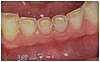

Usure des dents de la mâchoire inférieure par bruxisme.

Les dents du milieu ont perdu la moitié de leur hauteur initiale